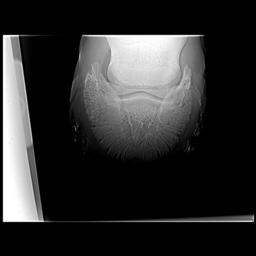

Posted on Thursday, Apr 5, 2007 - 1:11 pm: Dr O,I just read this article today after meeting with my vet and farrier yesterday regarding my horse's heel pain and I would like to get your input, if possible. I have had Remy for 6 years and have fought his low heel, long toe confirmation the whole time. In hindsight we did not do the right thing although we had the right idea. She said that if this had been managed properly for the past 6 years there would not be the damage there is now. I think the thing we missed was regular radiographs to see what was really going on. We just assumed that because he was not lame he was ok inside - the radiographs taken yesterday show that definitely was not the case. There is damage to the navicular, pedal osteitis, bone spurs and other things going on now. We have put him in 7 degree wedge pads with soft impression material. He walked off almost sound after the shoes were put on. I'm keeping a close eye on him because he can be sensitive to anything touching his sole as he has extremely thin soles. My vet said that it is important for sole growth that the frog had pressure - I had never heard that before. My vet said that it is possible that some healing can take place and he can return to regular work. She said that if the corrective shoeing doesn't work the next step would be injections - and she sounded pretty positive about the injections. We will continue to take regular xrays every 3 shoeings until we see the improvement we want. Does this sound like a good plan? I'm going to upload some radiographs that will give you an idea of what we are dealing with. I hope the thumbnails are large enough for you to view. I would greatly value any input you can give me. BTW I absolutely love this article! I'm going to print it and give it to my farrier. It's basically the same thing that he and my vet have said to me but it may have a couple extra insights. Thanks, Dawn Left front     Right front

Posted on Friday, Apr 6, 2007 - 6:36 am: Hello Dawn,I have moved your post into this new discussion. Using the radiographs as guides it would appear to me that the left could use around 7 degrees but the right a little less. This assumes the horse was standing square while radiographed. While radiographs are critical early in the assessment, because your feet do not appear to have any rotation of the coffin bone, you can assess proper balance without radiographs. This and how the foot responds to your work should be your guide to whether you have balanced these feet correctly. DrO |